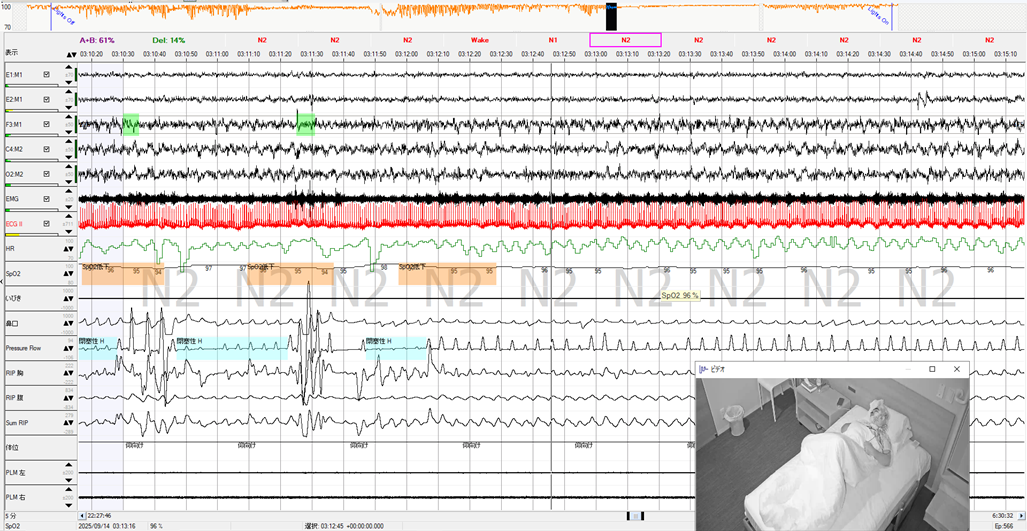

REI=16/時間、最低SpO2=86%、2%ODIが高値だったことで、PSG精査となりました。PSG結果はAHI=51.2回/時間と高値になりました。深睡眠も記録されていますが、AHIが高値となったのは、呼吸イベントの持続時間が短かったためと思われます。このトレンドで強い違和感を覚える点は、体位と呼吸イベントに出方に全く関係性が見えないことです。側臥位でも呼吸イベントが抑制されないかと思うと、同じ左側臥位で急に呼吸イベントが抑制されて深睡眠が記録されたり、後半仰臥位でも急に呼吸イベントが抑制されて、また深睡眠が記録されています。もう1点は、心拍数の高値もあり、HRトレンドの赤で示されているところは、心拍数が100回/分を超えている部分を表しています。

後半の仰臥位でも呼吸イベントが抑制された部分の波形を示しています。ビデオ画像では体幹は仰臥位ですが、わずかに頭位を右に傾けています。ただこの姿勢は閉塞性低呼吸が出現している間も同様でした。このタイミングから呼吸イベントが抑制されて、深睡眠が記録されていきます。ここでもう1点注目すべきは、枕の高さです。枕を2つ重ね、さらに下の枕は2つ折りにして高さを維持していたそうです。このことで上半身が半座位に近くなり、上気道が確保された可能性があります。また同じ姿勢でも呼吸イベントの出方が異なったのは、根本的に覚醒閾値が上昇することで、呼吸イベントが抑制されたと考えられます。